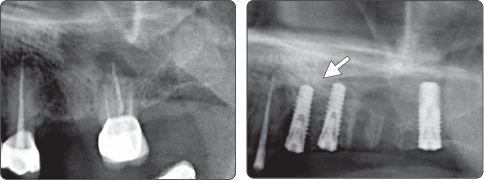

Sequence-Spreader

▶ Ridge Split and Block Bone Augmentation Technique with Spreader Drill (Ø4.0 Fixture).